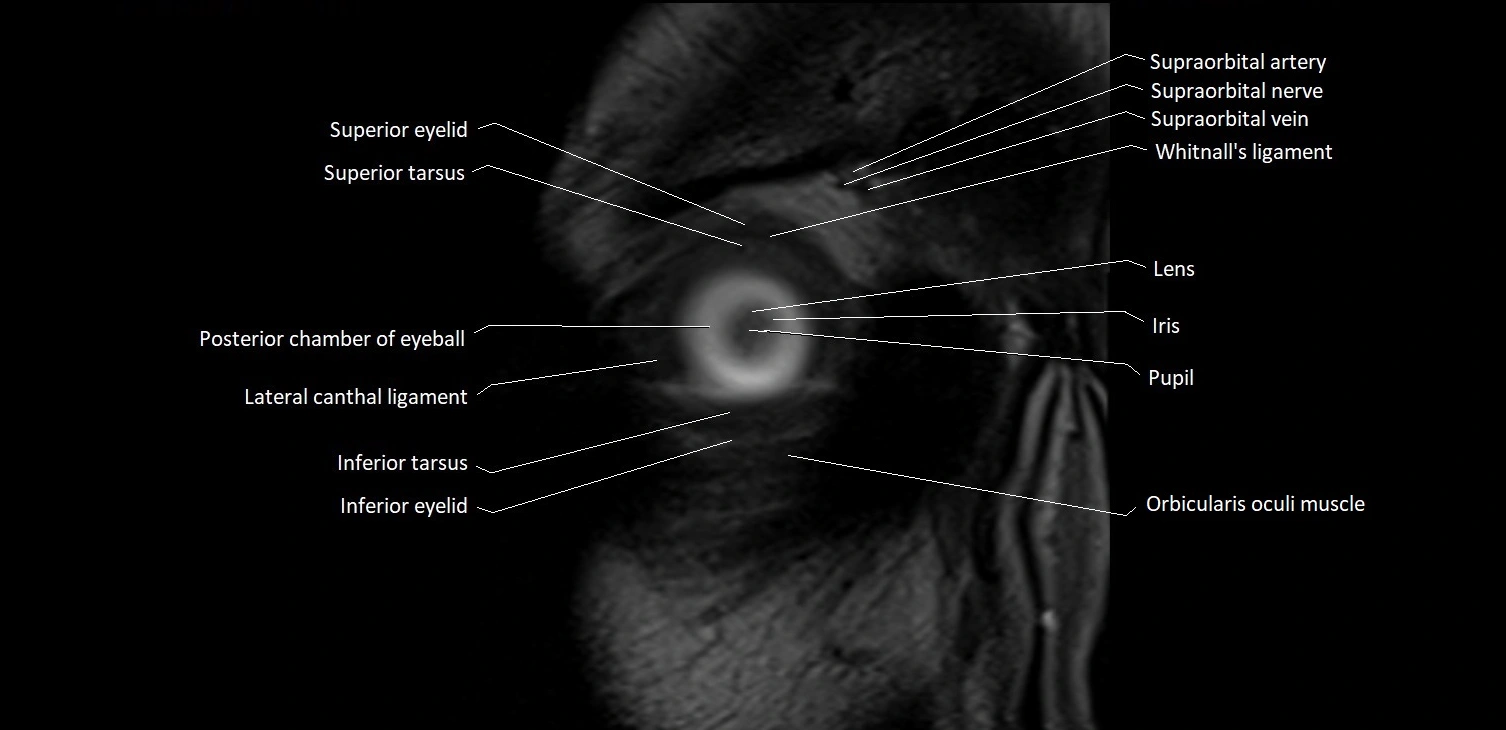

MRI images